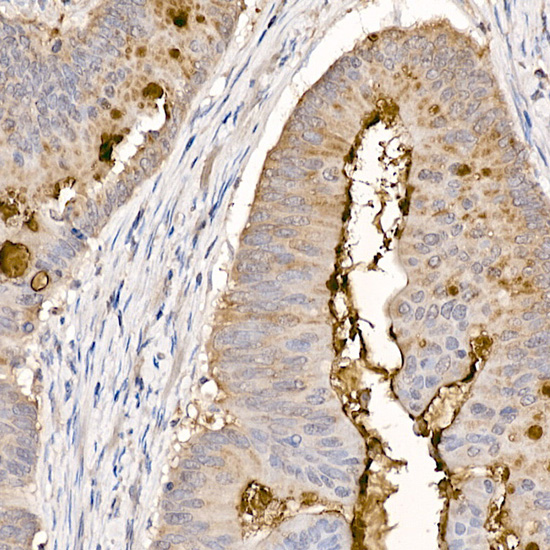

![MUC2 antibody [C3], C-term detects secreted MUC2 protein in human intestine by immunohistochemical analysis. Sample: Paraffin-embedded human intestine. MUC2 antibody [C3], C-term (GTX100664) diluted at 1:750.

Antigen Retrieval: Citrate buffer, pH 6.0, 15 min](https://www.genetex.com/upload/website/prouct_img/normal/GTX100664/GTX100664_42774_20170926_IHC-P_1_w_23060100_790.webp)